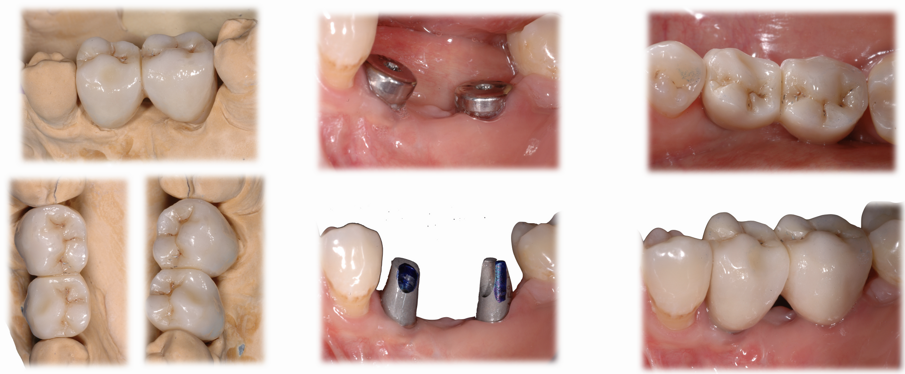

A sei mesi dall’intervento chirurgico la paziente venne sottoposta ad una nuova CBCT di controllo e questa evidenziò come i volumi stavano cambiando e l’osso innestato si stava mineralizzando al di sotto della lamina corticale, in bianco si nota la variazione volumetrica rispetto a quella che era la condizione iniziale (in blu) (Fig. 13). A dodici mesi dal primo intervento si decise di intervenire per inserire nella zona due impianti come da progetto iniziale, dopo aver anestetizzato la paziente con Articaina 1:200.000 una nuova incisione a mezza cresta permettè di scostare i lembi vestibolari e linguali per esporre la nuova cresta ossea ora con uno spessore di 8 mm nella parte posteriore e 6 mm nella porzione più anteriore. Questo consentì il posizionamento di due impianti a vite Bredent uno di diametro 4.5 x 8,5 mm di lunghezza (nel sito del molare) e uno di diametro 4 x 8,5 mm di lunghezza nel sito del secondo premolare13 (Figg. 14, 15).

Nella rx si vedono i due impianti con le viti di guarigione ad integrazione avvenuta. In figura 16 si nota l’ottimo aspetto dei tessuti peri-implantari con una adeguata quantità e qualità di gengiva cheratinizzata e le susseguenti corone in metallo ceramica successivamente cementate su due perni moncone in titanio fresati in laboratorio. Nelle foto successive si possono evidenziare le differenze dalla situazione iniziale (Fig. 17) a quella finale, in questo caso una foto di follow up a 48 mesi dalla finalizzazione del caso (Fig. 18). La rx a quattro anni dalla finalizzazione protesica evidenzia una situazione di perfetta stabilità, una cresta ossea ben mineralizzata ed un livello osseo inalterato dal momento della consegna del manufatto protesico definitivo (Fig. 19).